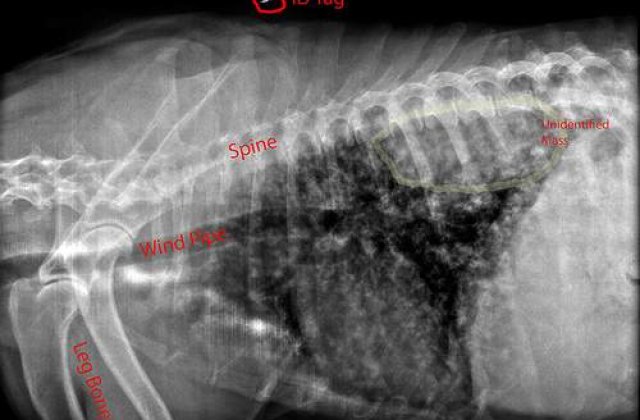

Ei au bagat-o imediat in operatie, pentru a extrage piesele de tacam inghitite de aceasta de-a lungul timpului, potrivit Agerpres. Uimitoarele imagini au fost realizate in urma cu 30 de ani, dar au fost publicate in aceasta saptamana, in premiera, intr-o revista medicala olandeza.